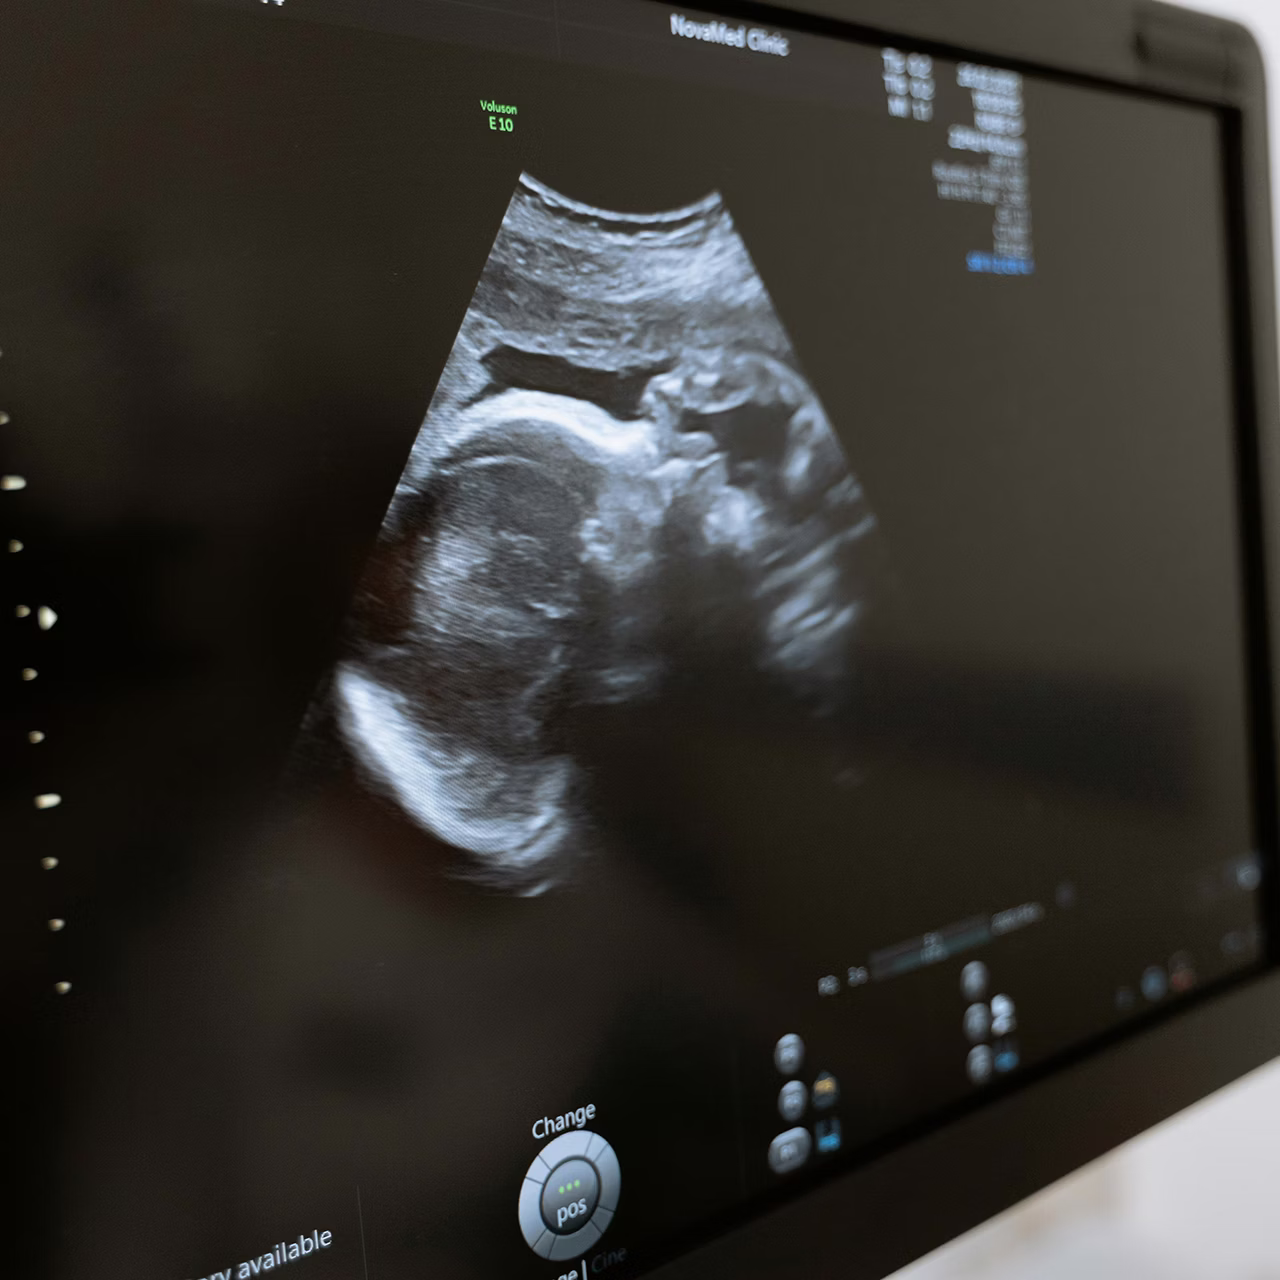

OB Ultrasounds

State-of-the-Art Imaging for Peace of Mind

Ultrasounds are a safe, non-invasive way to get a clear picture of what's happening inside your uterus. They use high-frequency sound waves to create images, without any radiation or harm. If you're dealing with an unexpected pregnancy, getting an ultrasound is a crucial first step to protect your health and make informed decisions.